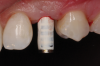

Fabrication of an immediate provisional restoration requires the selection of an appropriate implant provisional abutment and the creation of a tooth shell. Among other materials, commonly used implant provisional abutments are made from polyether ether keytone (PEEK), PEEK/titanium hybrid, or solid titanium (Figure 1). They can have engaging or non-engaging designs and are also sometimes available in various collar heights. Low-collar, engaging solid titanium provisional abutments offer advantages over others due to their high fracture strength, narrow dimensions, controllable emergence contours, ability to be torqued to high values, and robust seal at the implant abutment junction. However, they present the disadvantages of being slightly more expensive, harder to cut, and metallic in color. The metallic color can be mitigated by applying a flowable opaquing composite resin prior to attaching it to the crown shell. Solid titanium provisional abutments are best cut with a high-speed carbide bur or a metal cutting disc on a straight handpiece. They will heat up during cutting, but this can be easily managed by grasping them with a hemostat or analog and occasionally placing them into a cool water bath. The tooth shell can be fabricated from composite using a stone or resin model (Figure 2 through Figure 10) or from the patient's existing tooth or crown.

(1.) Implant provisional abutments come in three general material types: PEEK, PEEK/titanium hybrid, or solid titanium.

Figure 1